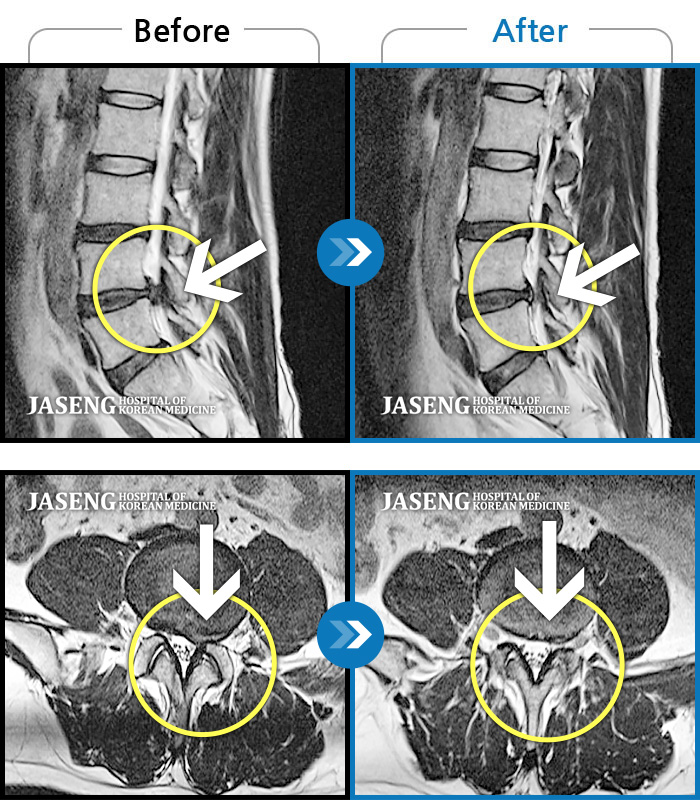

MRI 치료사례

허리 뻐근한 통증과 왼쪽 종아리 저림